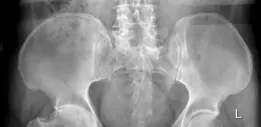

تُعد الأشعة السينية هي الخطوة الأولى والأساسية في تشخيص خشونة مفصل الفخذ. في حالة مريضنا، كشفت الأشعة السينية القياسية عن:

- تضيق شديد في المسافة المفصلية: وهو علامة مميزة لتآكل الغضروف.

- تكون نتوءات عظمية واسعة (Osteophytes): حول رأس الفخذ وحافة الحُقّ، خاصة في الجانبين الخلفي والعلوي.

- تصلب تحت الغضروف وتكيسات: في كل من الحُقّ ورأس الفخذ، مما يشير إلى تلف العظم تحت الغضروف.

- تشوه الحُقّ: أظهرت الأشعة السينية تشوهاً كبيراً في الحُقّ يتوافق مع الكسر السابق في العمود والجدار الخلفي.

- سوء الالتئام: وجود أدلة على سوء التئام، مع إعادة تشكيل غير منتظمة للعظم.

- هجرة رأس الفخذ: هجرة رأس الفخذ إلى الأعلى والجانب الإنسي، مع مكونات من انتباج الحُقّ (Protrusio Acetabuli)، مما يشير إلى تدهور كبير في الجدار الإنسي.

- تكلسات عظمية خارج المفصل (Heterotopic Ossification - HO): كانت مرئية حول المفصل، مما ساهم في تقييد نطاق الحركة بشدة.

الشكل 1: صورة شعاعية أمامية خلفية للحوض قبل الجراحة تظهر خشونة مفصل الفخذ الأيسر الشديدة بعد الصدمة مع تضيق المسافة المفصلية، وتكلسات عظمية واسعة، وهجرة رأس الفخذ إلى الأعلى والجانب الإنسي، مما يشير إلى فقدان كبير للعظم وتشوه في الحُقّ.